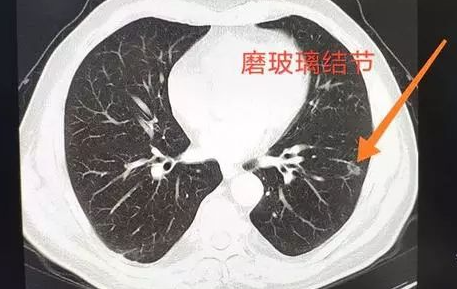

肺的磨玻璃结节就是指的在肺中有一些密度比较低的像磨渣样的玻璃,或者类似云雾一样的、小片状的、比较局限的结节,或者有时像一团小棉花一样的结节。由于它的密度相对来说不一样,密度比较低,和实性结节比没有那么高的密度,所以称之为磨玻璃结节。

磨玻璃结节也有单发的、多发的,原因也比较多,有的是原来病灶的激化导致,也有的是炎症、真菌感染导致,也有可能是特殊的病原体导致,当然这里边的结节可能是恶性肿瘤。单纯的结节,尤其是孤立的结节,还是要小心,要动态观察,特别是没有症状固定的结节就要随诊。